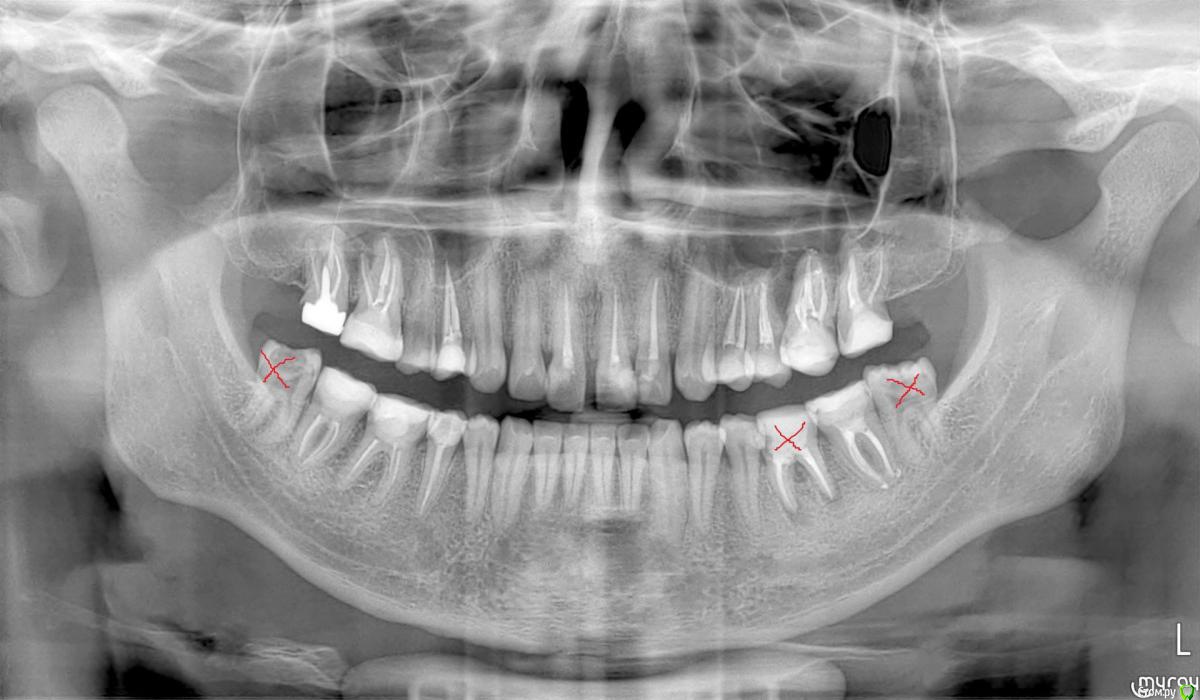

alex_ts Опубликовано 17 апреля, 2017 Поделиться Опубликовано 17 апреля, 2017 (изменено) Здравствуйте, мне 24 года и я имею наследственные проблемы с зубами, на данный момент большинство зубов пролечены по нескольку раз и многие зубы депульпированы. Также у меня с детства кривые зубы на верхней челюсти. Недавно впервые обратился к ортодонту за консультацией по постановке брекетов и мне сказали, что мертвые зубы довольно плохо поддаются перемещению, а у меня депульпированы в том числе передние резцы, ради которых я как раз и хочу эти самые брекеты поставить (большая диастема, 1цы выпирают вперед и в разные стороны). Плюс большинство жевательных зубов "нарощенны" пломбами, стоит циркониевая коронка на 17 зубе, а 36 зуба нет вовсе. Возможно ли в моем случае установить брекеты, или придется искать какую-то альтернативу? ПС, на снимке зачеркнуты удаленные зубы. Изменено 17 апреля, 2017 пользователем alex_ts Ссылка на комментарий

alex_ts Опубликовано 17 апреля, 2017 Автор Поделиться Опубликовано 17 апреля, 2017 Добавил фото, сбоку сделать не получается, если все таки необходимо - попробую сделать.. Ссылка на комментарий